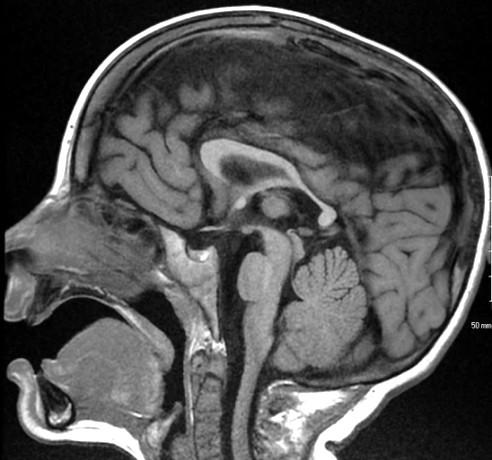

Sag T2 Cube Normal

Anterior commissure

Corpus Callosum

Rostrum, genu, body, splenium

Sella/Suprasella

ON, post pit bright spot, stalk

Midbrain

Patent aqueduct

Pons

“just right…”

Vermis

3 lobes

Cerebellar Tonsils